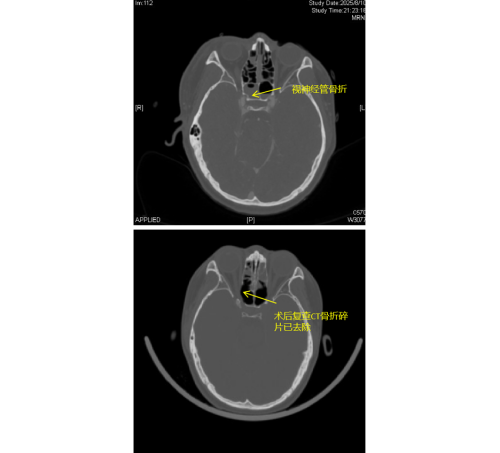

(南华大学附属长沙中心医院)急诊科。经检查发现,李琦存在颅底多处骨折、面颅多发骨折,尤其危急的是右侧视神经管骨折,碎裂的骨片直接压迫视神经及邻近的颈内动脉,导致右眼瞳孔散大、对光反射消失,视力完全丧失,病情极为危重。

由于视神经管周围解剖结构复杂,上方毗邻前颅底,下方紧邻颈内动脉和海绵窦,稍有不慎就可能导致脑脊液鼻漏、视神经断裂甚至颈内动脉破裂出血等严重后果,因此视神经的特殊位置被视为“手术雷区”。加之操作空间小,手术难度大,对于医生而言是一个巨大的挑战。视神经与鼻窦相邻,用鼻内镜经鼻窦进行视神经管减压手术,视野清楚、损伤最小。在手术过程中,康晓明医生利用高清鼻内镜,精准地清除了压迫视神经的骨折碎片,有效降低了神经压力。

手术完成后即刻观察到李琦右眼对光反射恢复灵敏,经过系统的治疗,其右眼视力已恢复至0.1,术后效果显著。目前,李琦正在进一步康复治疗中。此类高难度手术的成功,不仅展现了医院在多学科协作和急重症救治方面的综合实力,也为复杂颅底外伤患者带来了新的希望。